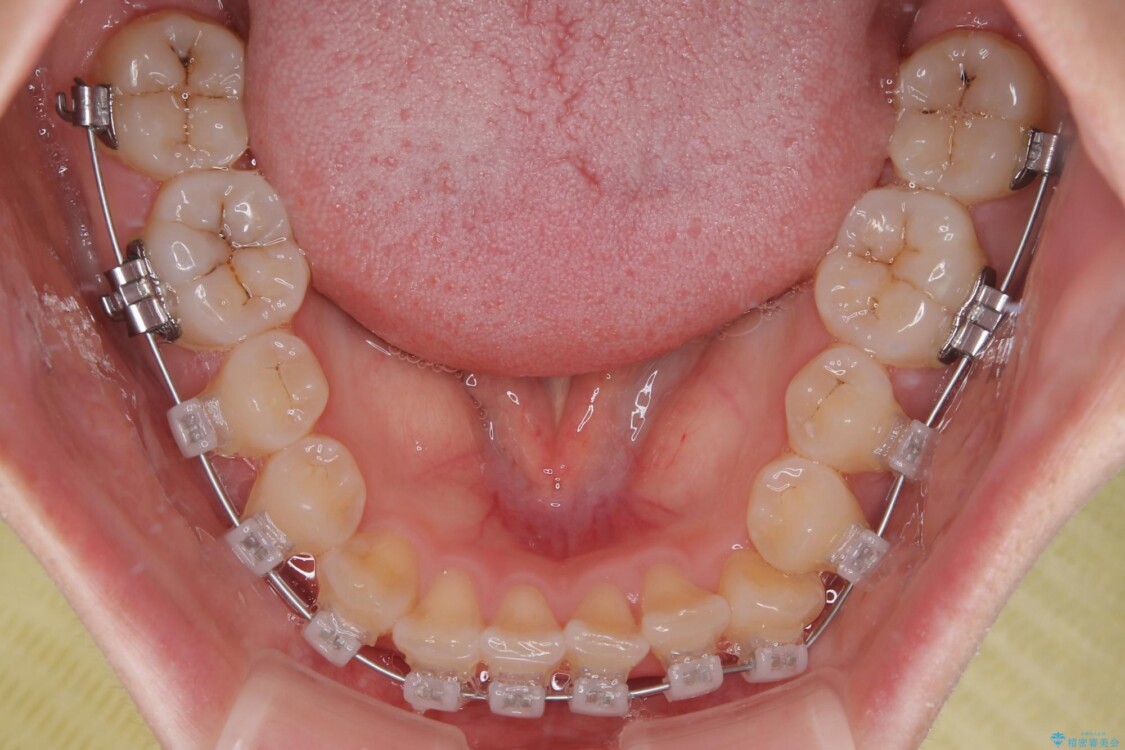

治療方法としては、装置の目立ちにくさと費用面のバランスを考慮して、プラスチック製のクリアブラケットとメタルワイヤーを組み合わせた矯正装置を使用することにしました。

治療途中

• 前歯のねじれ・ガタガタを10か月で改善!20代女性の矯正治療|クリアブラケットでむし歯になりにくい歯並びへ改善 治療途中画像